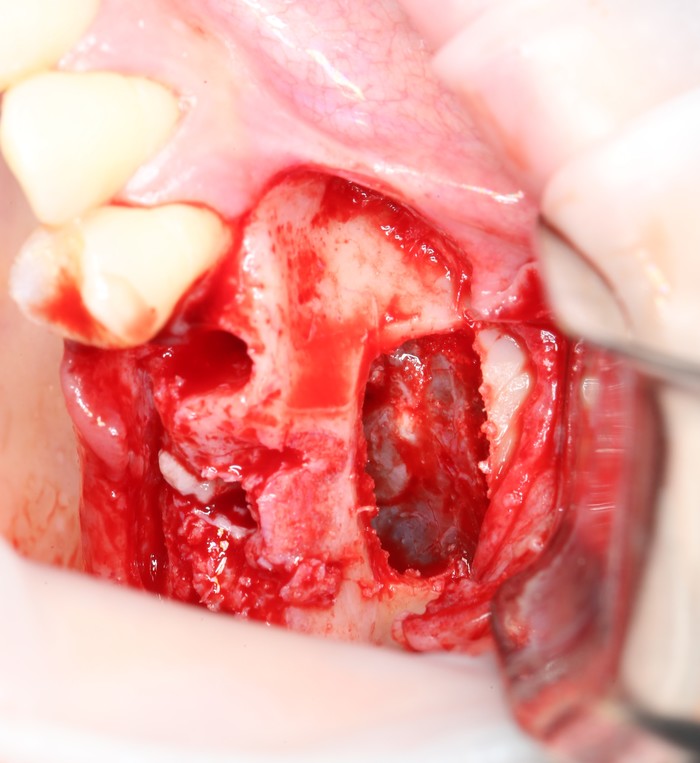

На верхней челюсти было дополнительно удалено два боковых резца с одномоментной установкой имплантатов, так же они были установлены в области четверок и шестых зубов. Дополнительно было проведено наращивание костной ткани - двусторонний синус - лифтинг. О том, что это такое, можно почитать ТУТ и ТУТ.